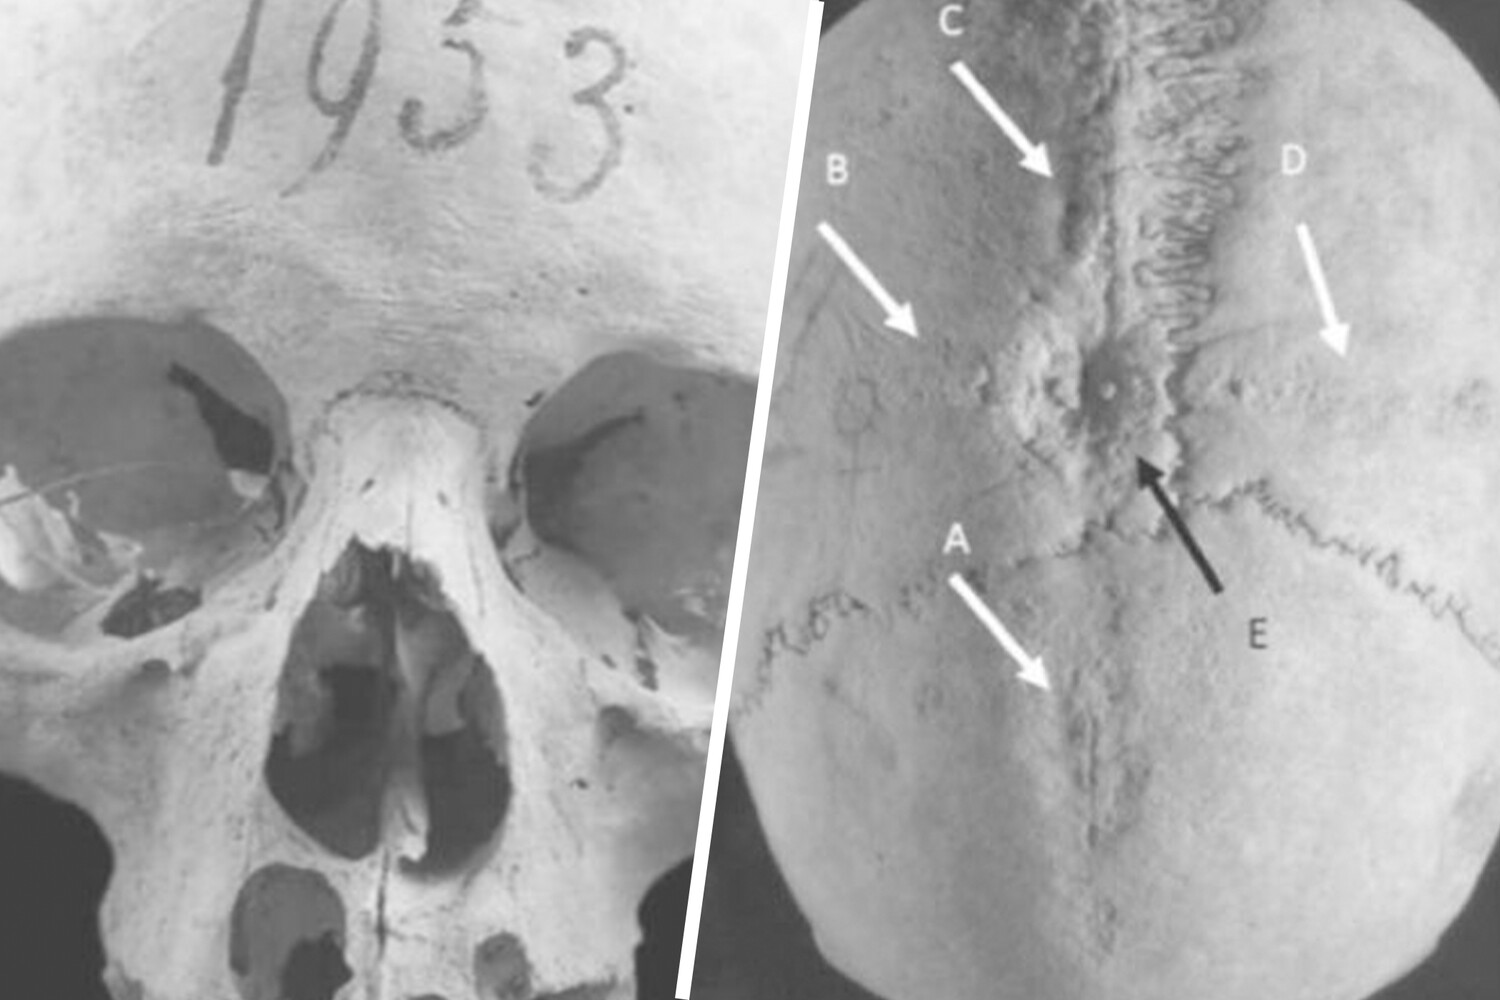

Группа археологов из Университета Экс-Марсель во Франции проанализировала череп средневековой женщины, которая жила в VI-VII веке в Италии, и нашли доказательства трепанации. Результаты опубликованы в журнале International Journal of Osteoarchaeology.

Авторы утверждают, что она перенесла по меньшей мере две операции на головном мозге. Это одно из немногих археологических свидетельств того, что трепанация проводилась женщинам раннего средневековья.

Исследованный череп был обнаружен в конце XIX века на кладбище Кастель-Трозино в центральной Италии. Он принадлежал женщине возрастом около 50 лет. Он был найден в двойном захоронении вместе с мужскими останками, а также бронзовой брошью, гребнем и золотыми нитями, что позволяет предположить, что пара принадлежала к местной элите.

«Мы обнаружили, что женщина пережила несколько операций. Первая операция прошла успешно. Вторая, вероятно, была проведена незадолго до смерти женщины», – отметили авторы.

Ученые провели КТ, согласно результатам которой у женщины были признаки гиперостоза (избыточное разрастание кости). Это заболевание часто встречается у женщин в период менопаузы, оно часто сопровождает другие проблемы со здоровьем, такие как судороги, головные боли, ожирение и диабет. Возможно, трепанация проводилась в лечебных целях, но также могла иметь и ритуальное значение.